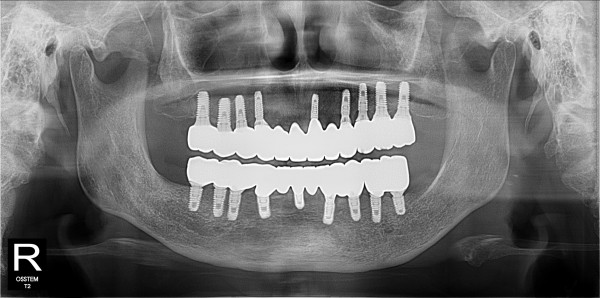

네비게이션 임플란트 최고관리자 0건 23-11-07 18:39 본문 풀케이스 네비게이션 임플란트 목록 이전글네비게이션 임플란트 23.11.07 다음글네비게이션 임플란트 23.11.07 댓글목록 0 댓글목록 등록된 댓글이 없습니다.